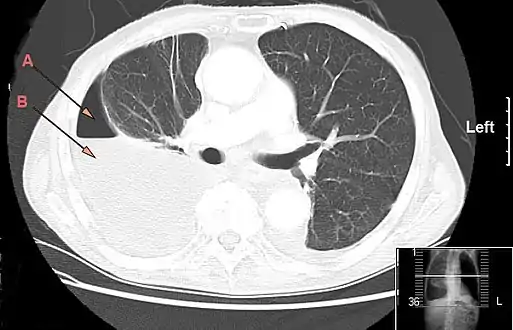

Lungs

Empyema